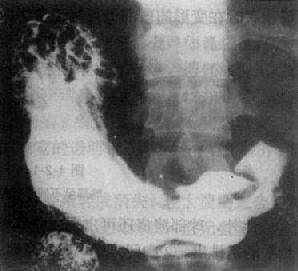

图4-2-15 胃底癌(蕈伞型)

胃底贲门区巨大肿块,不规则